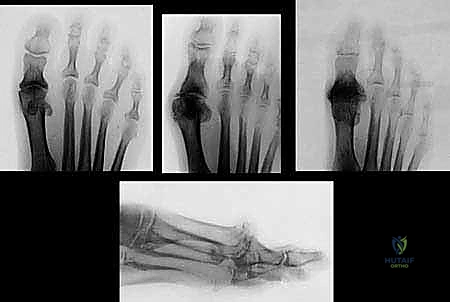

- التصوير الإشعاعي (X-rays):

وهو الأداة الذهبية لتشخيص تيبس إبهام القدم. تُظهر الأشعة السينية بوضوح: - تضيق المسافة بين العظام (دليل على تآكل الغضروف).

- وجود النتوءات العظمية (Bone Spurs).

- أي تكيسات عظمية أو تشوهات في شكل المفصل.

جدول 1: تصنيف مراحل تيبس إبهام القدم (Coughlin and Shurnas Classification)

يعتمد الأطباء، وعلى رأسهم الأستاذ الدكتور محمد هطيف، على هذا التصنيف العالمي لتحديد شدة المرض واختيار العلاج الأنسب:

| المرحلة (Grade) | الأعراض السريرية | التغيرات الإشعاعية (أشعة X) | نطاق الحركة (Dorsiflexion) |

|---|---|---|---|

| المرحلة 0 | ألم خفيف عرضي، لا يوجد ألم أثناء المشي العادي. | طبيعية أو تغيرات طفيفة جداً. | طبيعي أو مقيد بشكل بسيط (40-60 درجة). |

| المرحلة 1 | ألم متقطع، خاصة عند أقصى درجات الانثناء. | نتوء عظمي ظهري صغير، الحيز المفصلي سليم. | تقييد بسيط (30-40 درجة). |

| المرحلة 2 | ألم معتدل إلى شديد، تيبس ملحوظ، ألم قبل الوصول لأقصى انثناء. | نتوء عظمي واضح، تضيق في الحيز المفصلي الظهري. | تقييد ملحوظ (10-30 درجة). |

| المرحلة 3 | ألم شديد ومستمر حتى في أوقات الراحة، صعوبة بالغة في المشي. | تضيق شديد في الحيز المفصلي بالكامل، نتوءات عظمية كبيرة، تكيسات تحت الغضروف. | تقييد شديد (أقل من 10 درجات). |

| المرحلة 4 | نفس أعراض المرحلة 3، مع ألم دائم حتى عند تحريك المفصل سلبياً (بواسطة الطبيب). | تدمير كامل للمفصل، اختفاء الحيز المفصلي تماماً. | تيبس شبه كامل. |